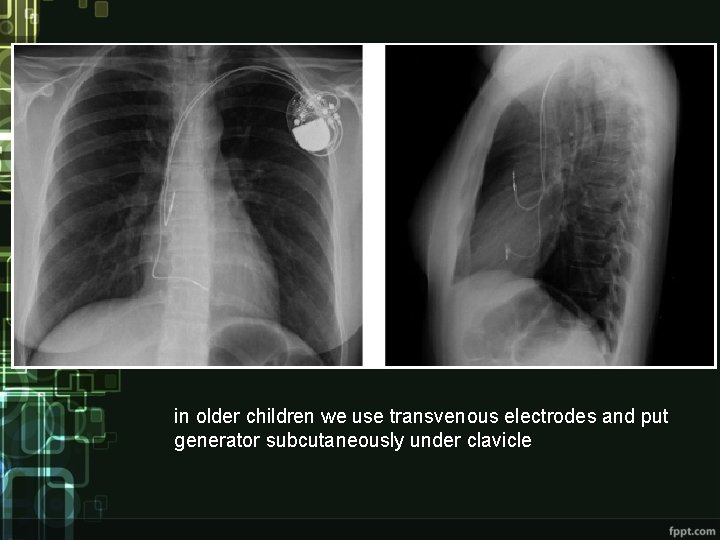

Treatment • pharmacological - euphyllin • pacemaker

in older children we use transvenous electrodes and put generator subcutaneously under clavicle